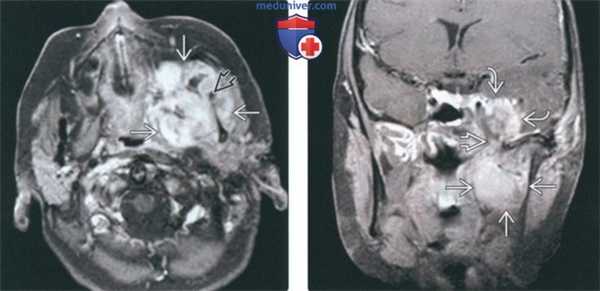

(Слева) При МРТ Т1ВИ в аксиальной проекции определяется объемное образование с сигналом промежуточной интенсивности, которое деформирует жевательное пространство и смещает кпереди заднюю стенку левой верхнечелюстной пазухи. Во всех последовательностях видны небольшие участки низкой интенсивности сигнала, которые представляют собой кальцификаты.

(Справа) МРТ Т2ВИ в аксиальной проекции, этот же пациент. Новообразование имеет гиперинтенсивный сигнал, характерный для опухолей хрящевой ткани. (Слева) МРТ Т1ВИ с КУ, аксиальная проекция, этот же пациент. Образование имеет неоднородную структуру и интенсивно накапливает гадолиний.

(Справа) КТ с КУ в аксиальной проекции, костное окно, этот же пациент. Определяется крупное новообразование, в толще которого «рассеяны» кальцификаты, образующие кольца и арки. Это типичные хрящевые кальцификаты. Наличие кальцификатов обычно говорит о низкой степени злокачественности опухоли.

(Слева) КТ в костном окне, аксиальная проекция. Типичная хондросаркома височно-нижнечелюстного сустава низкой степени злокачественности. Определяются небольшие кальцификаты дистрофической природы (либо кальцифицированный матрикс самого образования) и обширная деарукция/ремоделирова -ние суставной ямки.

(Справа) MPT Т2ВИ в аксиальной проекции, тот же пациент. Определяется дольчатое гиперинтенсивное образование с четкими контурами, которое окружает мыщелок нижней челюсти.